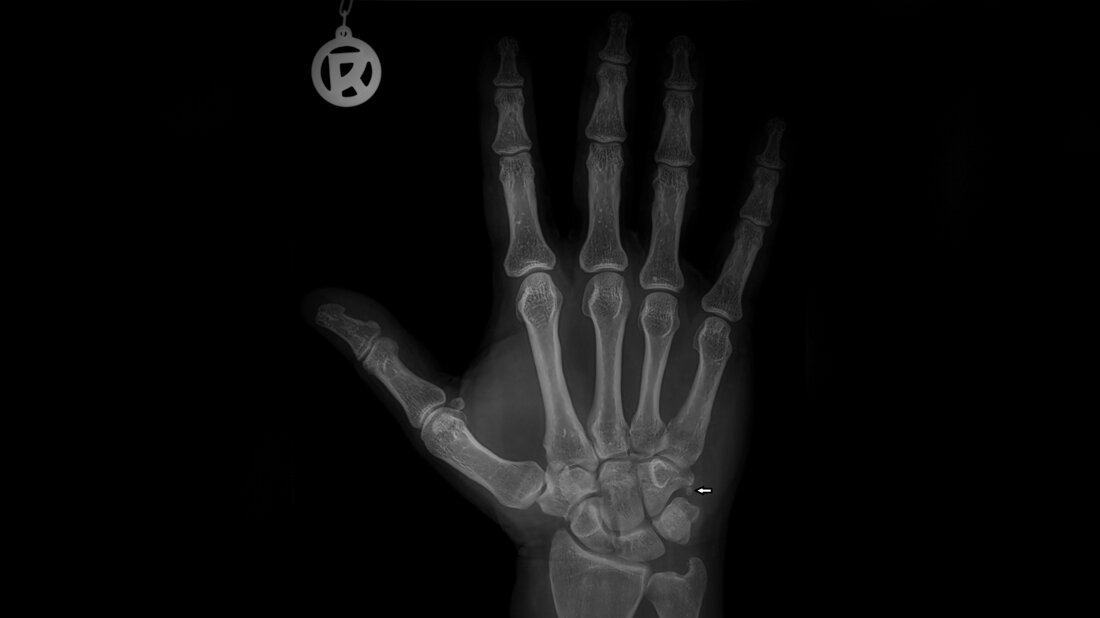

Akzessorische Knochen und Varianten der Hand und des Handgelenks sind nicht ungewöhnlich. Die Prävalenz und die Verteilung von Sesambeinen und Akzessoria der Hand sind abhängig von verschiedenen Populationen und ethnischen Gruppen sehr variabel.

Accessory bones and variants are not uncommon at the region of hand and wrist. The prevalence and distribution of sesamoid and accessory bones in the hands is quite variable between different populations and ethnic groups.